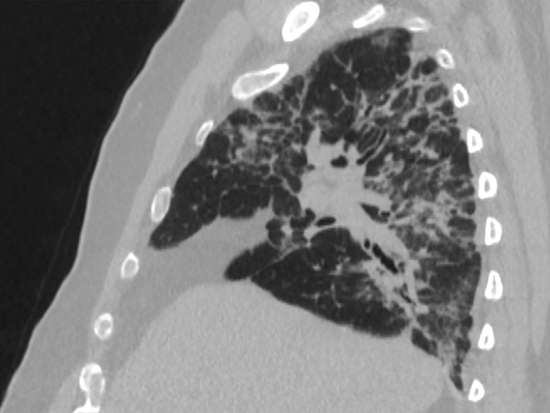

Mice were given bleomycin for 12 days to establish lung fibrosis, and then treated daily until 21 days with ABT-199, whose medical form is known as Venetoclax, a medication approved by the United States Food and Drug Administration for use in several forms of leukemia. Control bleomycin mice had lung fibrosis with widespread collagen deposition. The bleomycin mice that received ABT-199 had normal lung architecture at 21 days and no collagen deposition.

Pulmonary fibrosis is a chronic disease showing aberrant remodeling of lung tissue. Idiopathic pulmonary fibrosis is the most common form of pulmonary fibrosis and has a high mortality rate within three to five years. Currently approved medications have limited efficacy.